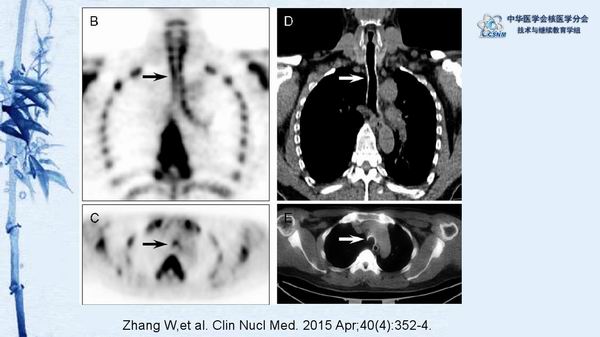

讲座15:复发性多软骨炎-张卫方